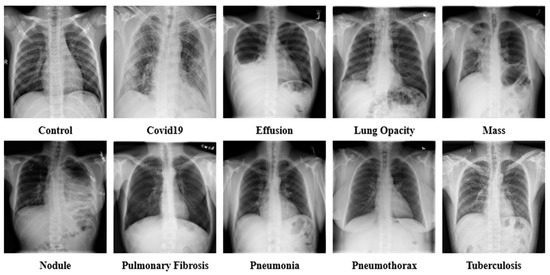

3. Datasets

| No. | Disease | Data | Reference |

|---|---|---|---|

| 1. | Control | 13,672 | [21,22,23,26,27,28,31] |

| 2. | COVID-19 | 15,660 | [21,22,24,25,28,31] |

| 3. | Effusion | 13,501 | [30,32,33,34] |

| 4. | Lung Opacity | 7179 | [31,35] |

| 5. | Mass | 5603 | [30,33] |

| 6. | Nodule | 6201 | [30,33] |

| 7. | Pulmonary Fibrosis | 3357 | [28,30,33] |

| 8. | Pneumonia | 9878 | [21,22,23,28,31] |

| 9. | Pneumothorax | 6870 | [29,30,33] |

| 10. | Tuberculosis | 3184 | [24,26,27,28,36] |